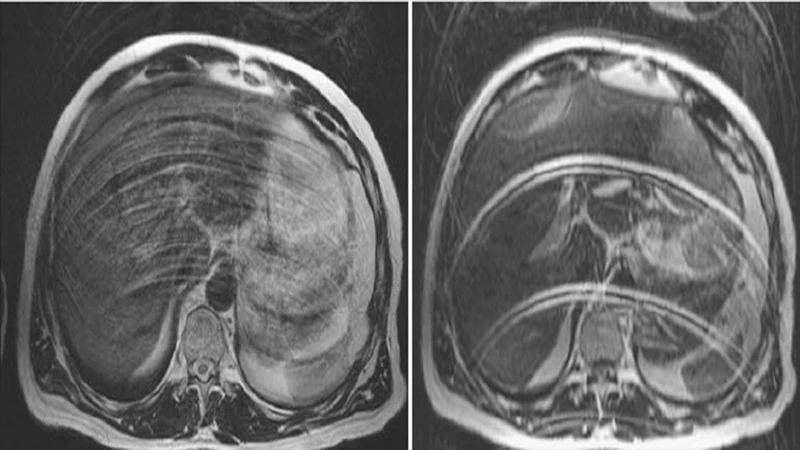

3. Aliasing or "Wrap-Around" Artifact (MRI)

This is a specific MRI artifact that occurs when the Field of View (FOV) is set too small for the body part being scanned. Anatomy that is outside the FOV gets "wrapped around" and appears on the opposite side of the image.

- Appearance: A portion of the anatomy (e.g., the nose in a brain scan, or an arm in an abdomen scan) appears superimposed on the other side of the image.

- Cause: The scanner misinterprets the spatial location of signals coming from outside the prescribed FOV.